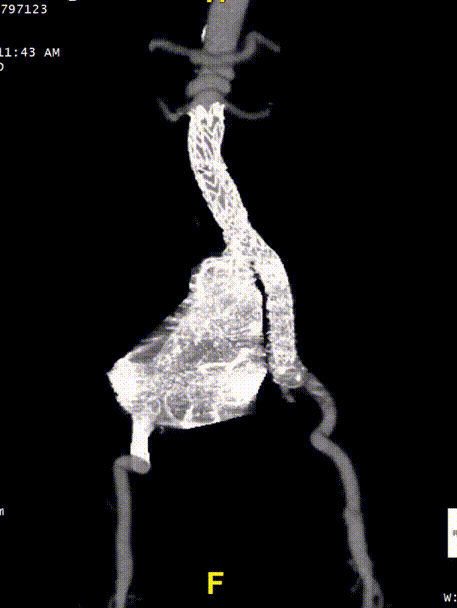

五、术后随访

患者术后进行随访,支架形态良好,瘤体隔绝良好,分支血管通畅,预后满意。

gore医疗怎么样「漫腹精论」髂合时宜 精益求精——双MOB球囊导管辅助腹主动脉覆膜支架急诊治疗破裂巨大髂动脉瘤_https://www.jmylbn.com_新闻资讯_第28张

gore医疗怎么样「漫腹精论」髂合时宜 精益求精——双MOB球囊导管辅助腹主动脉覆膜支架急诊治疗破裂巨大髂动脉瘤_https://www.jmylbn.com_新闻资讯_第29张

gore医疗怎么样「漫腹精论」髂合时宜 精益求精——双MOB球囊导管辅助腹主动脉覆膜支架急诊治疗破裂巨大髂动脉瘤_https://www.jmylbn.com_新闻资讯_第30张

gore医疗怎么样「漫腹精论」髂合时宜 精益求精——双MOB球囊导管辅助腹主动脉覆膜支架急诊治疗破裂巨大髂动脉瘤_https://www.jmylbn.com_新闻资讯_第31张

gore医疗怎么样「漫腹精论」髂合时宜 精益求精——双MOB球囊导管辅助腹主动脉覆膜支架急诊治疗破裂巨大髂动脉瘤_https://www.jmylbn.com_新闻资讯_第32张

gore医疗怎么样「漫腹精论」髂合时宜 精益求精——双MOB球囊导管辅助腹主动脉覆膜支架急诊治疗破裂巨大髂动脉瘤_https://www.jmylbn.com_新闻资讯_第33张

gore医疗怎么样「漫腹精论」髂合时宜 精益求精——双MOB球囊导管辅助腹主动脉覆膜支架急诊治疗破裂巨大髂动脉瘤_https://www.jmylbn.com_新闻资讯_第34张